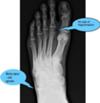

I would really appreciate any advice I can get, because I don't know where to turn. Locals are not very helpful, because they are just not good at judging a good doctor from a bad one. If you are better, the doctor was good; if not, he was bad. They seem to be unaware that doctors are not following any kind of standard routine in dealing with patients, and don't mind a three minute visit with a specialist with other patients standing around in the examination room breathing down your neck. By the way, I am 35 years old, 188cm, and 75 kg, so don't tell me to lose weight! I hope you don't mind if I add my latest x-ray. Perhaps you can see something the doctors don't.

That X-ray is too small for me to read. Could you send me the original scans. Did you digi them with your camera or are the digital X-rays? The lateral and oblique ankle and foot are usually more useful. But there is no substitute for a good physical exam. Is the fixation in the subtalar joint, or the cuboid... the metatarsals etc.

I e-mailed the x-rays you mentioned, and I also sent two x-rays from almost two years ago, and from what I can tell, there is a difference in the second toe, although I am a bit baffled as to how that could have occurred, since I have cut way back on exercising in the last two years due to the pain it was causing my back.

I'm afraid I don't see any signs of Freiberg's disease. I suspect, obviously without examining your foot this is very tentative, you have a case of metatarsalgia second to an old ankle sprain. You can see a bony spur forming in the calcano-cuboid joint, a sure sign of an old untreated injury.